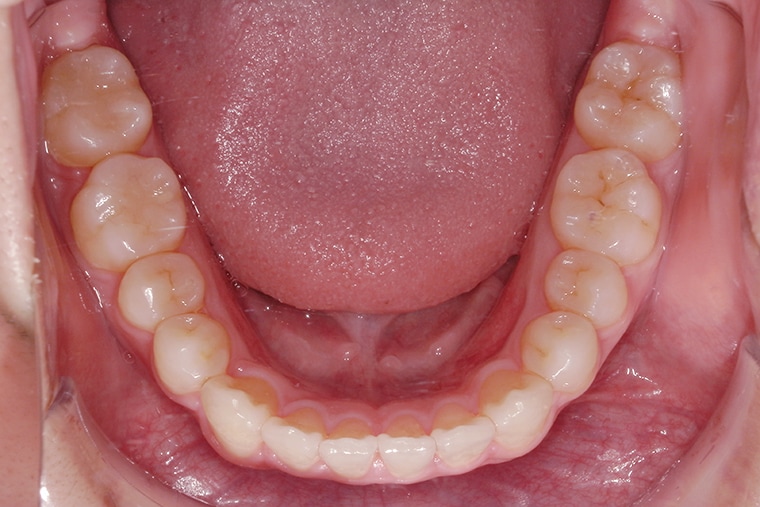

38歳男性ガタガタな歯のマウスピース矯正-矯正期間10ヶ月

- 治療費用

- 550,000円(税込)

- 治療期間

- 10ヶ月

- 性別

- 男性

- 年齢

- 38歳

- 抜歯

- 無し

- 治療方法

- マウスピース矯正(インビザラインLite)による治療方法

- 治療リスク

- 1日22時間の装着時間を守らないと治療期間が遅くなり、歯並びの質が悪くなります

上の前歯のガタつきと、下の前歯が内側に入っているのが気になっており、ずっと治したいと思っていました。

シミュレーション通りにいくのかという不安はありましたが、きれいにしたいという気持ちが強く、矯正を始めました。

治療中は細やかに対応していただき、安心して通うことができました。矯正をして本当によかったと感じています。